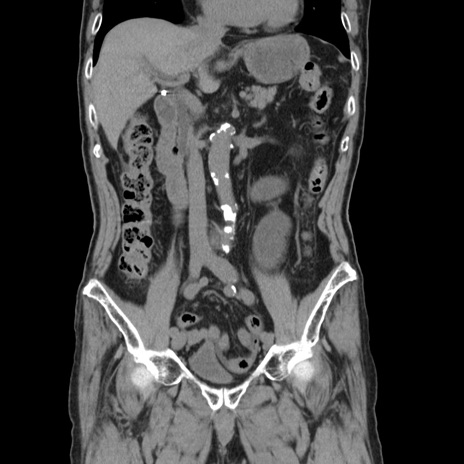

症例24(冠状断像)

【症例】80歳代男性

【主訴】左側腹部痛、嘔吐

【現病歴】本日早朝より左腹部に痛みあり。昼頃嘔吐認めたため、救急要請。

【既往歴】直腸癌(Mile手術)、胆摘

【身体所見】意識清明、BT 35.9℃、BP 221/93mmHg、SpO2 97%(RA) 、腹部:左ストーマ周囲に限局性の腹部膨隆あり。 膨隆部自発痛・圧痛あり・軟。

【データ】WBC 7700、CRP 0.09